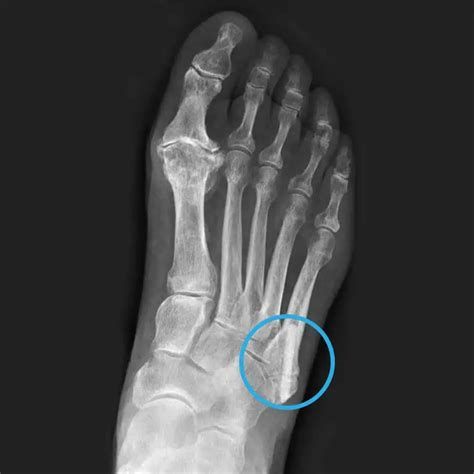

발목 제외 발골절 수술 비용 차이의 원인

발(발목 제외) 골절 수술 비용은 다양한 요인에 의해 차이가 크게 발생합니다. 평균적으로 73만~410만 원대까지 비용이 분포하며, 아래의 세부 요소들이 비용 차이를 결정짓습니다.

1. 골절의 부위와 심각도

- 위치: 발등, 발가락, 중족골 등 골절된 구체적 부위에 따라 수술 난이도와 방법이 달라집니다.

- 복잡성: 단순 골절(깨끗하게 부러짐)과 분쇄 골절(여러 조각으로 부러짐), 개방성 골절(뼈가 밖으로 튀어나옴) 등 골절의 형태 및 복합 정도가 높아질수록 비용이 오릅니다.

2. 수술 방법 및 사용 재료

- 내고정술, 외고정술 등: 금속 핀, 나사, 플레이트 등 사용 재료와 기술 수준에 따라 비용이 다릅니다.

- 수술 방식: 최소침습 수술, 절개 방법, 마취 종류 등에 따라도 수술비가 변동될 수 있습니다.

- 특수재료 및 비급여 항목: 건강보험 적용 여부에 따라 본인 부담 비용의 차이가 있으며, 비급여 재료(특수 금속, 수입재료 등)가 쓰이면 비용이 크게 증가합니다.

3. 입원 기간 및 병실 등급

- 입원 기간: 수술 후 회복과 재활 여부, 합병증 발생 등에 따라 입원일 수(평균 약 11일, 최대 32일)가 길어질수록 입원비가 추가됩니다.

- 병실 등급: 일반실, 1인실, 특실 등 입원 병실 유형에 따라 입원료 차이가 큽니다.

4. 의료기관 규모 및 지역

- 대형 병원 vs. 일반 병원: 상급종합병원, 대학병원 등은 의료진, 장비, 시설 차이로 인해 비용이 높아질 수 있습니다.

- 지역별 의료 수가: 대도시와 지방 병원 간의 진료비 차이도 존재합니다.

5. 추가 검사 및 재활 치료

- 정밀 검사: X-ray, CT, MRI 등 추가 촬영 및 정밀 진단 시 검사비가 발생합니다.

- 재활치료, 약물, 보조기: 수술 후 재활치료(물리치료 등)나 보조기 착용, 약제비 등도 총비용에 포함됩니다.

정리:

발(발목 제외) 골절 수술 비용의 차이는 주로 골절의 형태와 부위, 수술 난이도, 사용 재료와 의료기관, 입원 기간 및 병실 등급, 추가 검사·치료 등의 종합적인 요소에 의해 결정됩니다. 정확한 비용은 반드시 진료받는 병원에 문의해야 하며, 건강보험 및 실손보험 가입 여부도 본인 부담금에 큰 영향을 줍니다